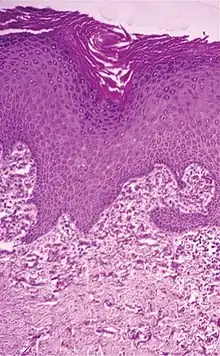

| Elastosis perforans serpiginosa | Degenerated elastic fibers and transepidermal perforating canals (arrow in image points at one of them)[18] | ![]() |